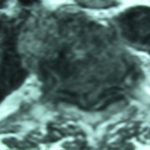

Εικ. 4: Μαγνητική τομογραφία της Θ.Μ.Σ.Σ. εγκάρσια λήψη, ακολουθία Τ1 & Τ2

Διαπιστώνεται η καταστροφή του μεσοσπονδυλίου δίσκου, φλεγμονώδεις περισπονδυλικές μάζες πλαγίως και προσθίως και οπισθίως ύπαρξη επισκληριδίου αποστήματος